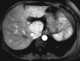

Adenomatosis

An adenoma is a benign tumor of epithelial tissue with glandular origin, glandular characteristics, or both. Adenomas can grow from many glandular organs, including the adrenal glands, pituitary gland, thyroid, prostate, and others. [Source: Wikipedia ]